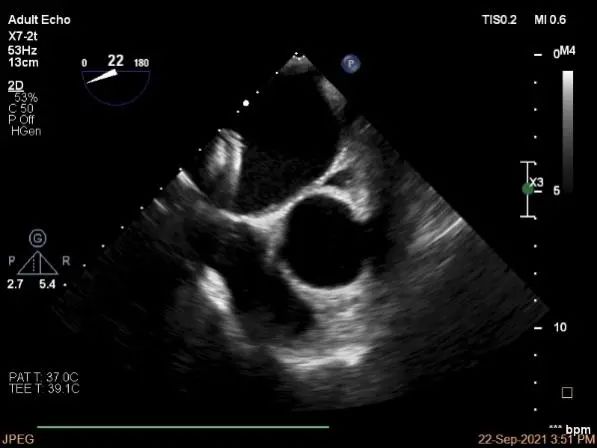

三维评估两个夹子位置

3D-color再次确定未见残余分流

评估瓣口条件,平均跨瓣压差:4mmHg

肺静脉血流频谱恢复正常